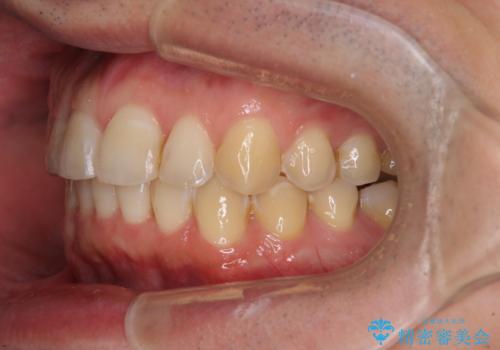

ディープバイトと叢生を解消 インビザライン矯正

- 前歯のデコボコを強い咬みしめを気にして来院された患者様です。

インビザラインを用いて、前歯の叢生を解消するとともに、ディープバイトを改善していくこととしました。

ディープバイトが改善されたことで、顎への負担が軽減され、更には上顎前歯の突出感も改善することができました。